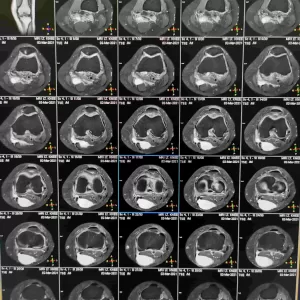

Ilustratie Patologie Genunchi

Ecografie / RMN – pot detecta modificări articulare, prezența tofilor sau a altor complicații. Vezi cat costa un RMN la Genunchi!